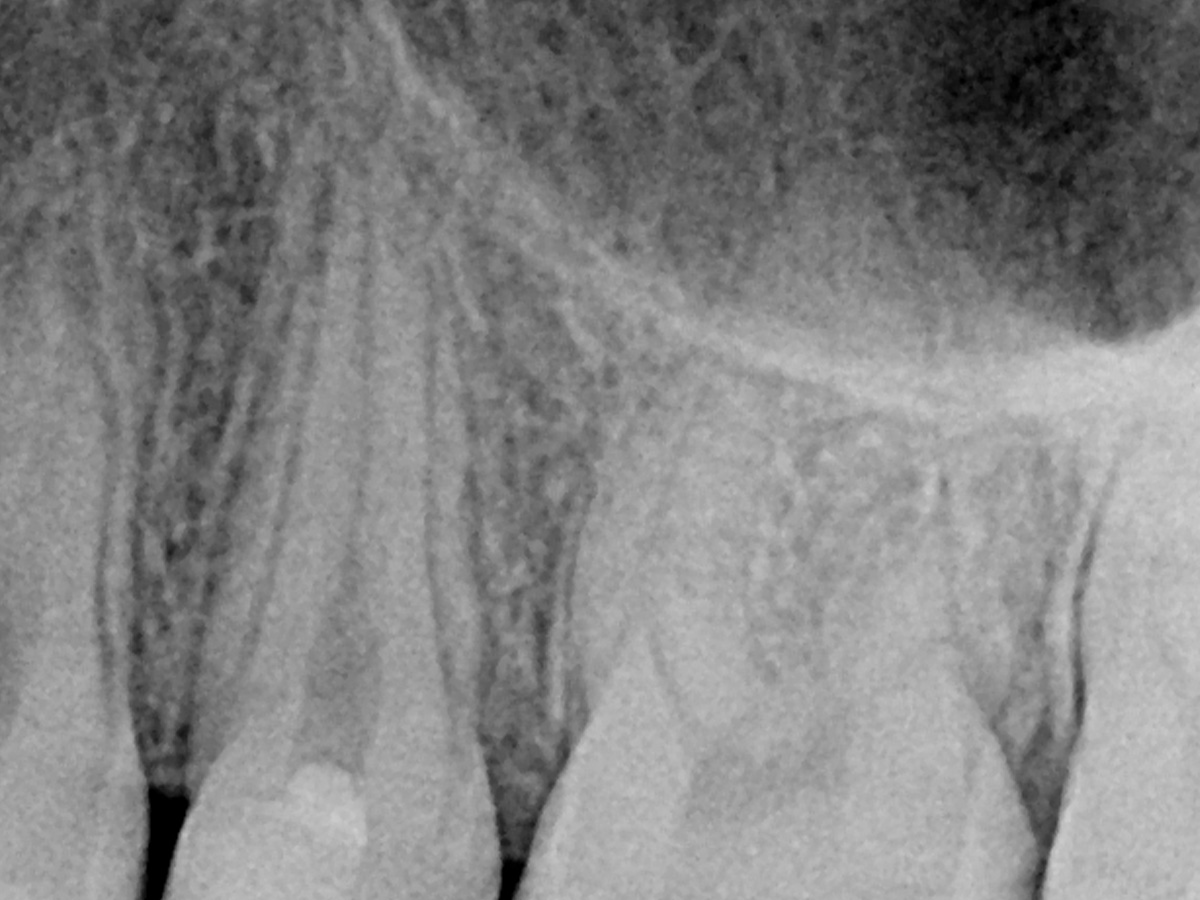

Abbildung 13

Post-Op: Direkt nach der Kappung.

Abbildung 14

Recall: Aufnahme des Zahnes 25 fünf Monate nach Kappung.